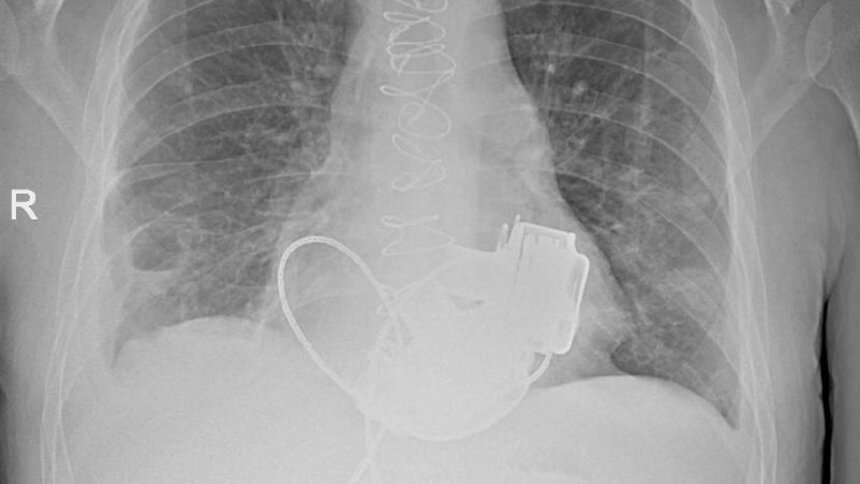

Пульса нет вообще, а вместо сердца — два пламенных мотора: в России впервые пациенту имплантировали оба желудочка - Новости Калининграда | Фото: Комитет по здравоохранению Санкт-Петербурга

Фото: Комитет по здравоохранению Санкт-Петербурга

В Санкт-Петербурге врачи готовят к выписке пациента, который теперь живёт без пульса. В конце ноября 2025 года 36-летнему мужчине имплантировали одновременно левый и правый искусственные желудочки сердца. Об этом рассказали в городском комитете по здравоохранению.

По словам главного врача Мариинской больницы Игоря Реутского, когда Антон поступил в стационар, показатели работы сердца были такими, будто человек уже не жив, а мёртв. При этом из-за сопутствующих осложнений трансплантация сердца была невозможна.

«Операция продолжалась около 4 часов. Для наших специалистов самым сложным было синхронизировать работу двух искусственных желудочков сердца, но с этой задачей мы успешно справились. Это доказывает высокий уровень развития кардиохирургии в нашем городе». — отметил главный внештатный специалист по сердечно-сосудистой хирургии Санкт-Петербурга Геннадий Хубулава.

Врачи надеются теперь вновь встретиться с Антоном, так как имплантация искусственных желудочков — «мостик» к трансплантации сердца, которую пациент теперь сможет дождаться.